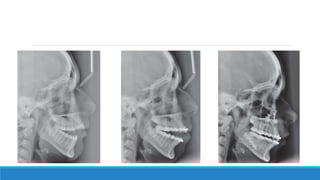

2. Pre-surgical Orthodontic

Pre-treatment Orthodontic decompensation After surgery